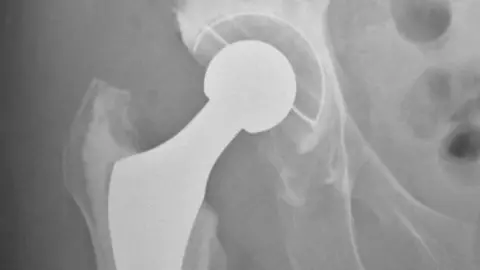

Most hip and knee replacements 'last longer than thought'

Getty ImagesEight out of 10 knee replacements and six out of 10 hip replacements last as long as 25 years, says a large study from the University of Bristol.

University of BristolHow long do they last?

Hip replacements: 89% lasted 15 years, 70% lasted 20 years, 58% lasted 25 years

Total knee replacements: 93% lasted 15 years, 90% lasted 20 years, 82% lasted 25 years

Partial knee replacements: 77% lasted 15 years, 72% lasted 20 years, 70% lasted 25 years